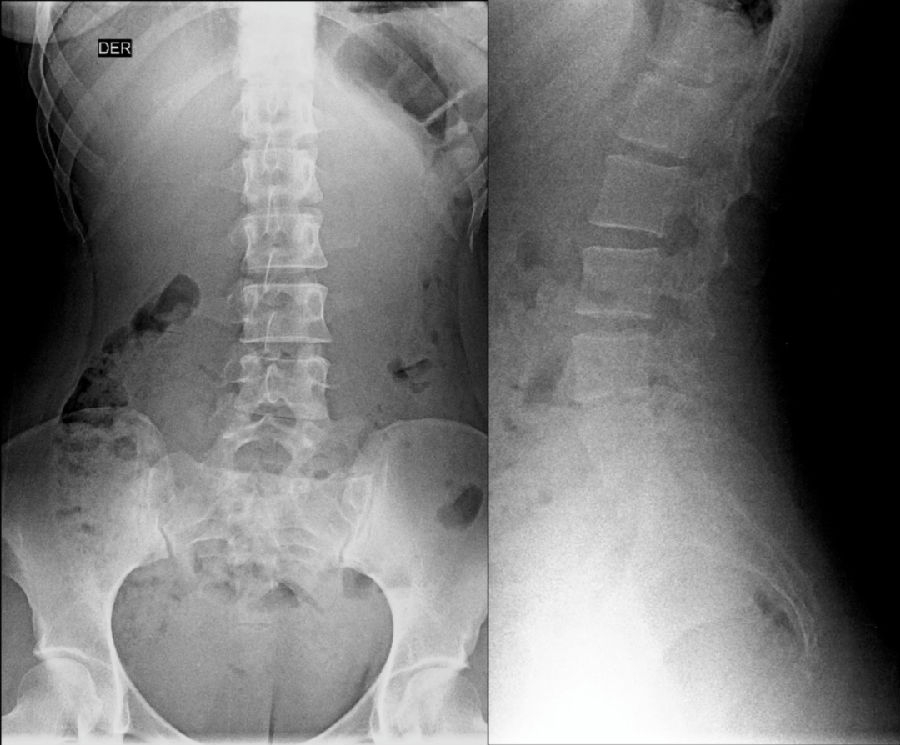

腰椎骶化及骶椎腰化均是椎骨发育的异常,腰椎骶化是指第五腰椎外型类似骶椎形态,并构成骶骨块的一部分,一侧或两侧横突肥大呈翼状,与骶骨发生融合或形成假关节。骶椎腰化是指第一骶椎演变成腰椎样形态,即第一骶骨从筋骨块中游离出来形成第6个腰椎。

腰椎骶化

骶椎腰化

如何在临床阅片准确判断是一个很重要的问题,这里介绍一个最准确的判断方法。

这是一个最关键和准确的鉴定方法,国内著名骨放射学家杨世埙教授指导过,只要大家留意关注腰椎横突"三长/四翘/五宽",L3横突是最长的,L4横突是上翘的,L5横突最宽,特别用在胸椎腰化合并L5骶化的时候比较实用。